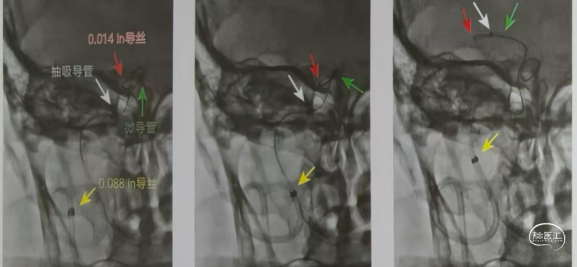

ACE68或GT68抽吸导管根据血管迂曲塑形后内衬0.018in微导丝支撑前行通过迂曲血管到达大脑中动脉M1段,输送支架取栓或抽吸取栓。如果血栓负荷小,尽量选择5F中间导管或ACE60抽吸导管能够顺利通过迂曲血管建立通路。下图所示。

环状迂曲血管操作技术要点:

建立通路和抽吸导管输送的插图。

Nueron MAX长鞘开始应置于颈动脉360°环的近端,以避免发生颈动脉夹层(图1)。

沿着微导丝-微导管-抽吸导管组成的三同轴系统,可使长鞘安全地沿360°环向远端推进,通过C1段环状迂曲部位,同时并不会强行改变这种血管迂曲的状态。随后在长鞘高到位支撑下容易将抽吸导管继续向M1段的血栓部位推进。如图所示。